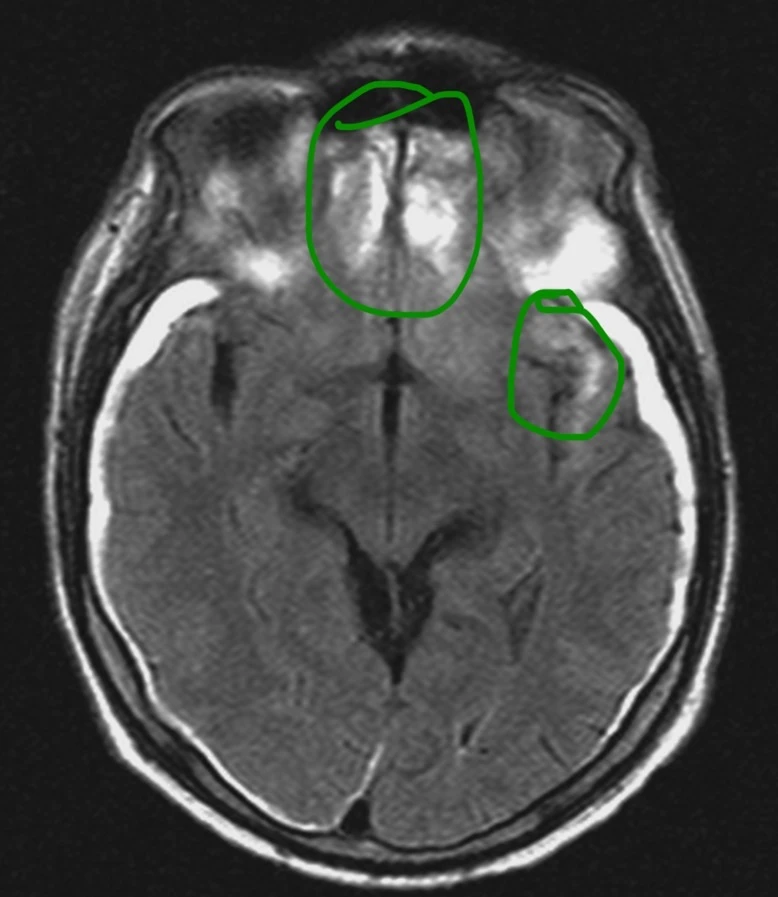

Мужчина 35 лет, месяц назад упал с высоты двух метров, сейчас не полностью ориентирован в месте и времени. Типичная (кроме мозжечка справа) картина травматического аксонального повреждения 3 степени (с поражением ствола). Множественные мелкие точечные и линейные микрокровоизлияния, вокруг части из них видны глиоз/отек. А вот в мозжечке, реально, нечасто такое увидишь. Но бывает. Типа, как вот здесь: